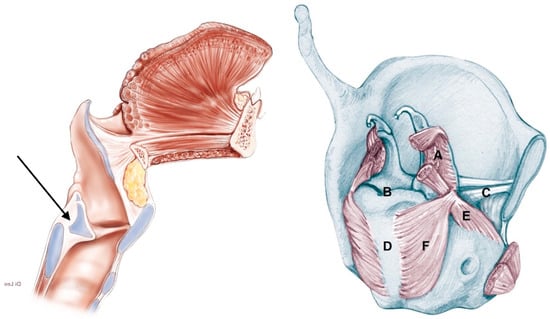

2.3. Pattern of Arytenoid Fixation

- Supraglottic carcinoma encasing the arytenoid from above with its fixation due to weight effect, without direct involvement of the CAU (Figure 2):

- The tumor infiltrates the superior paraglottic space (SPGS) and the thyro-arytenoid muscle (TAM) without direct involvement of the crico-arytenoid unit (CAU), with evaluation of the following radiological parameters: superior paraglottic space (SPGS), TAM, inferior paraglottic space (IPGS), crico-arytenoid joint (CAJ) and cricoid plate.